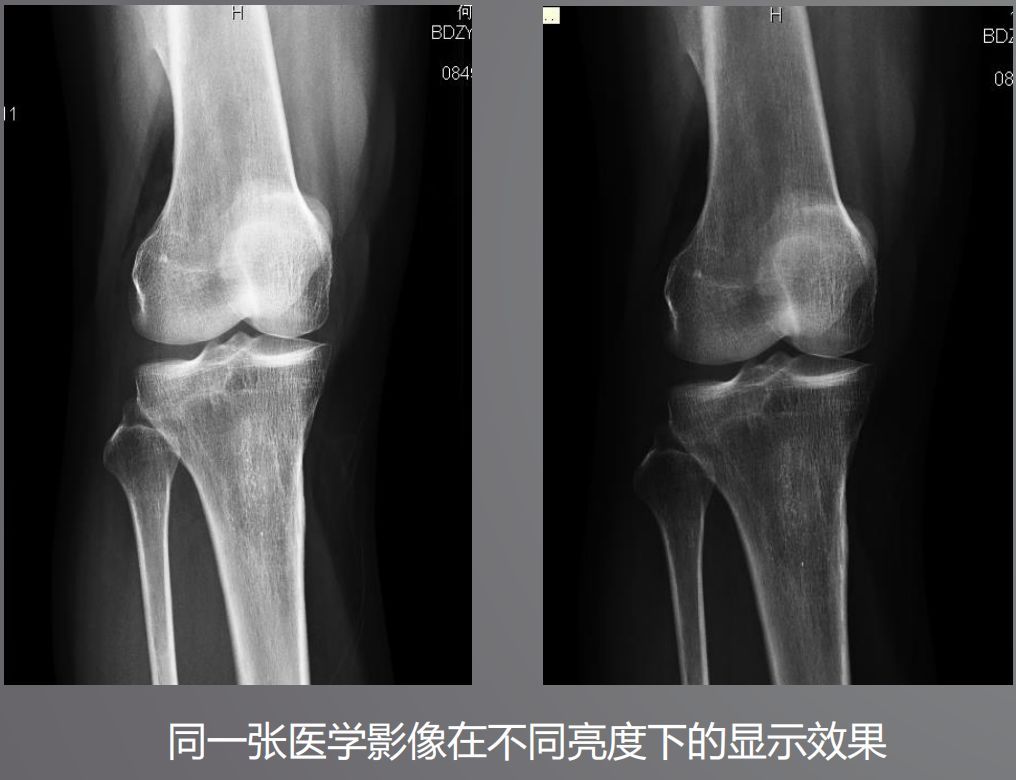

三、高亮度

高亮度從字面上就非常好理解了,回想在傳統膠片時代,閱片都是直接夾在大大的發光白板上。而平時我們瀏覽網頁或者看視頻并不需要那么高的亮度,導致普通顯示器亮度偏低,達不到醫用閱片的標準。

根據DICOM Part14規定,所有醫學顯示器必須符合GSDF的標準,確保顯示區域亮度符合一致性。而普通顯示器是不需要刻意符合這個標準的。

醫用顯示器通過系統測量和調整每一個像素的亮度,降低中心和角落之間亮度和色彩的不均勻性,通過減少這些差異,確保顯示器每個顯示區都能符合DICOM GSDF標準。